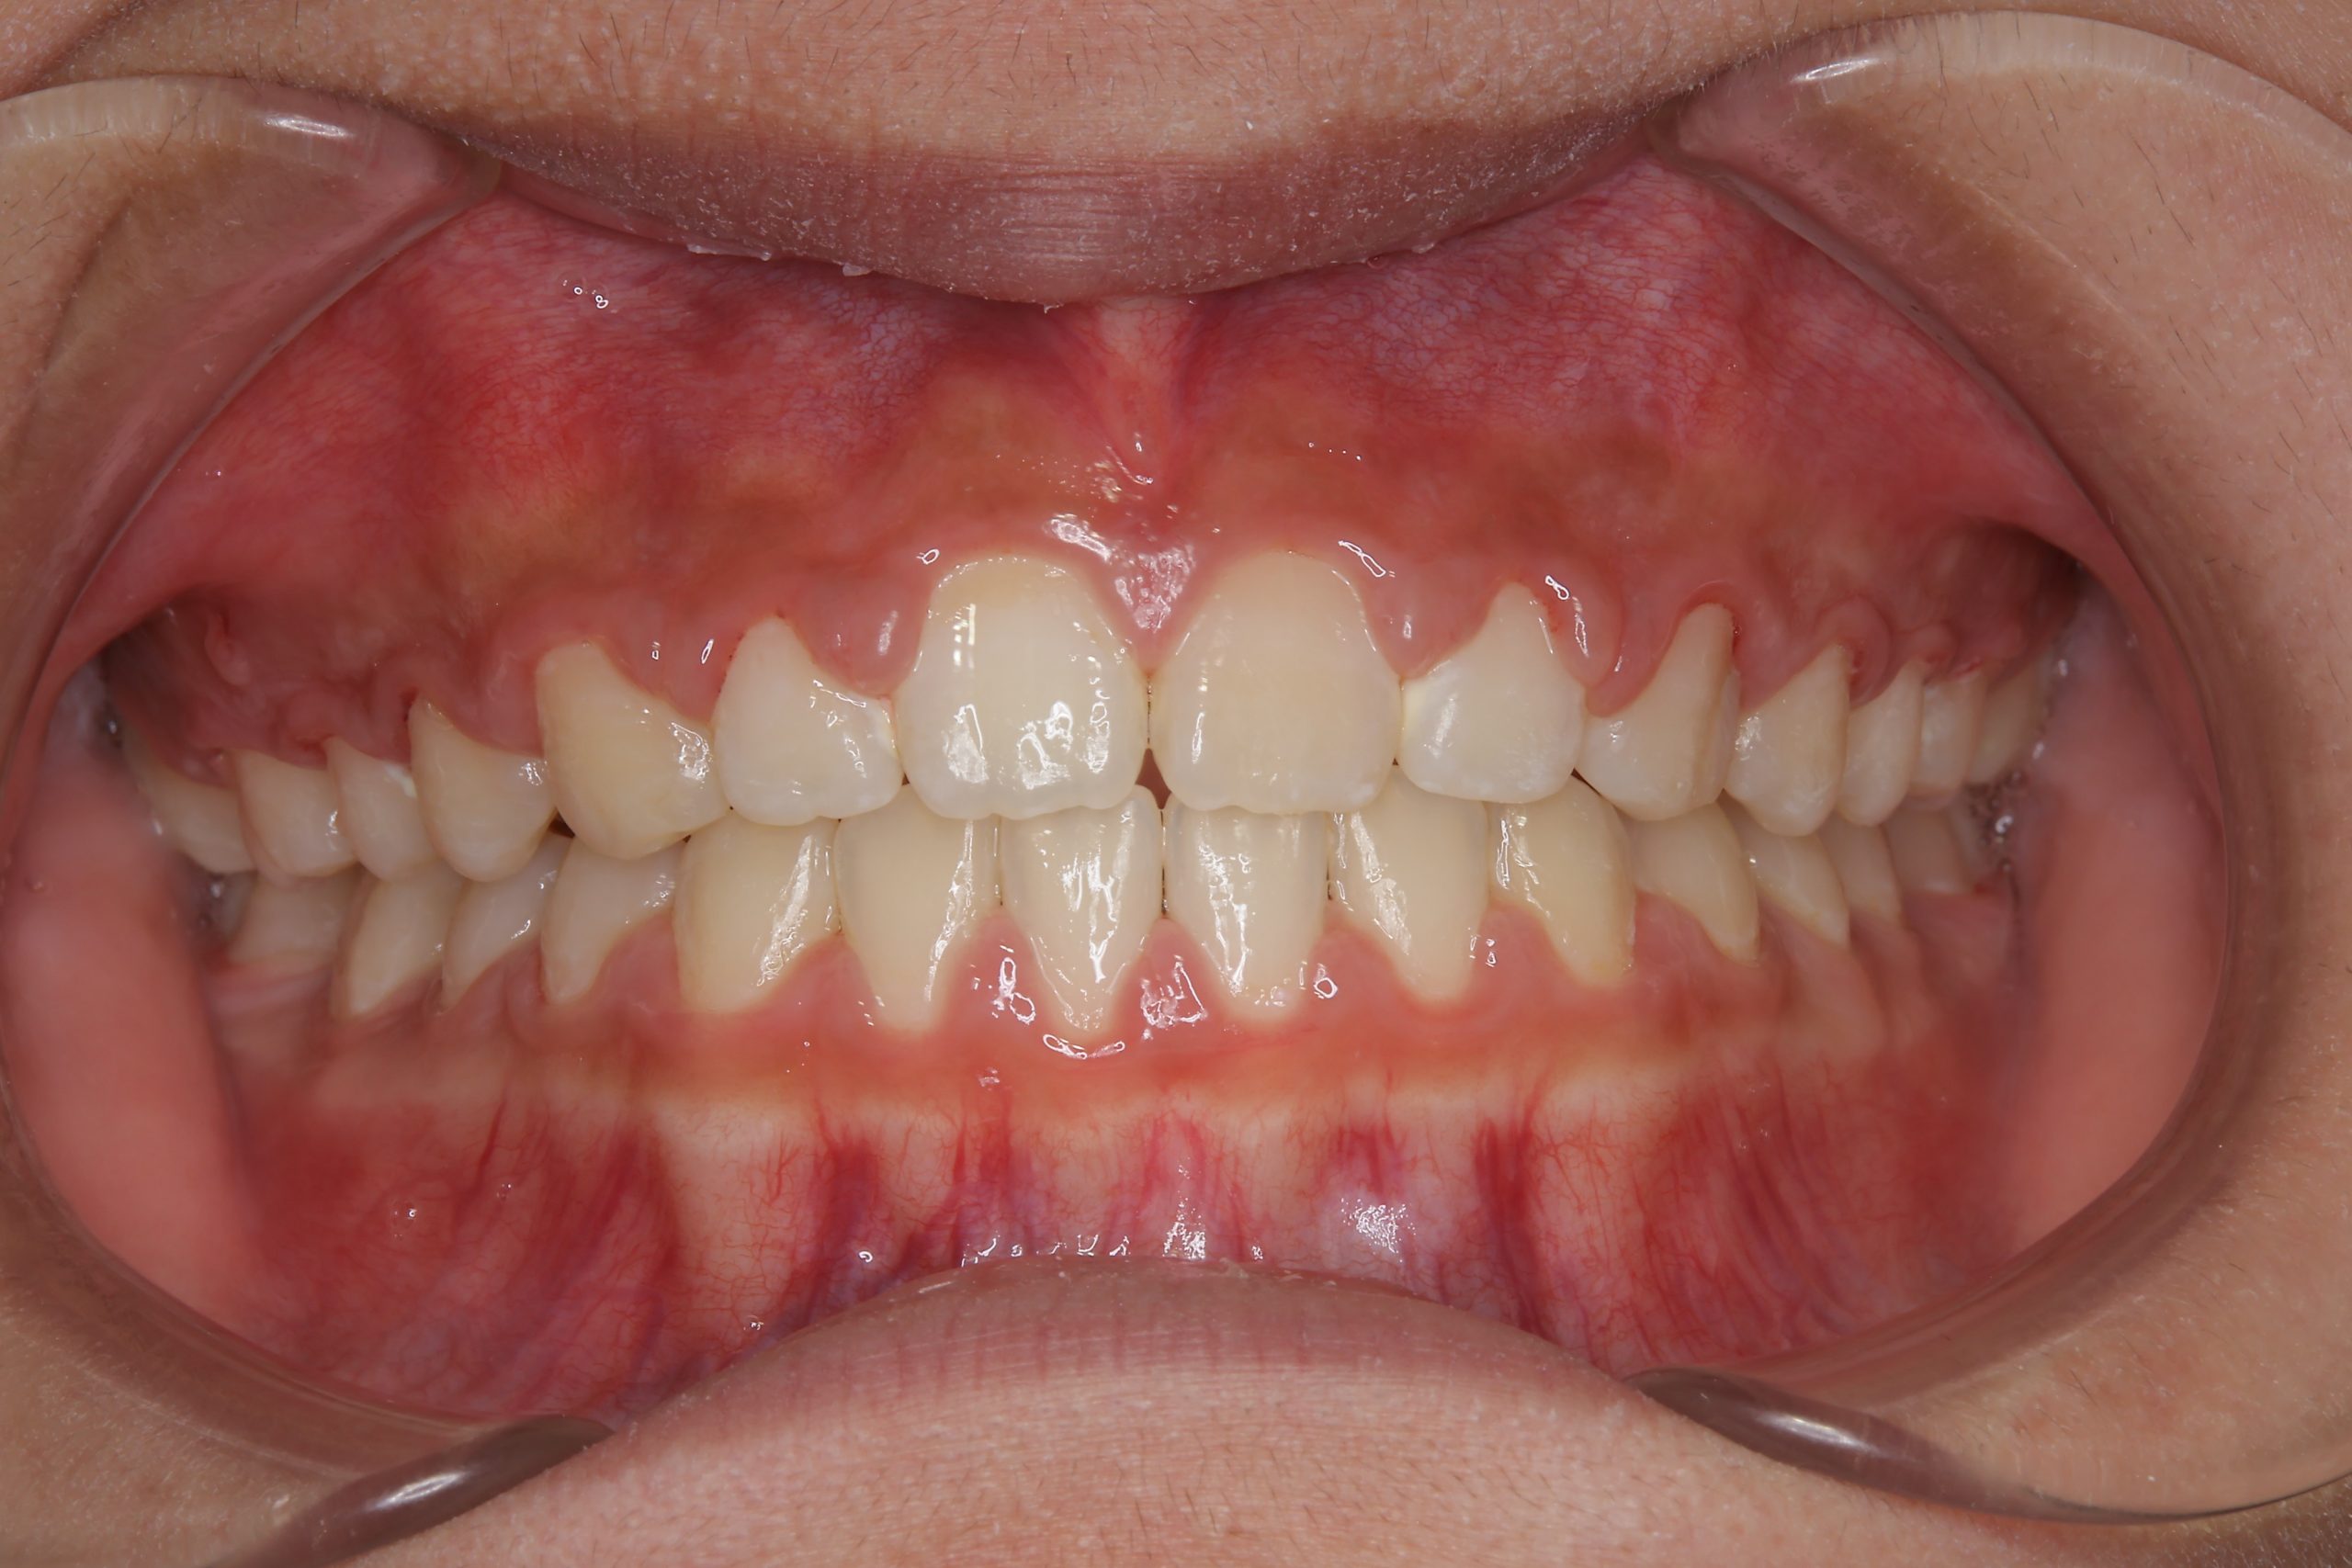

ビフォー

主訴 上前歯が出ている|よく口が開いている

施術内容 上顎急速拡大装置と下顎リンガルアーチを用いて上下顎骨を拡大した。

その後マルチブラケット装置を用いて

非抜歯で歯牙を配列し良好な咬合を獲得した。

鼻閉症状は改善した。

治癒期間 2年10か月間